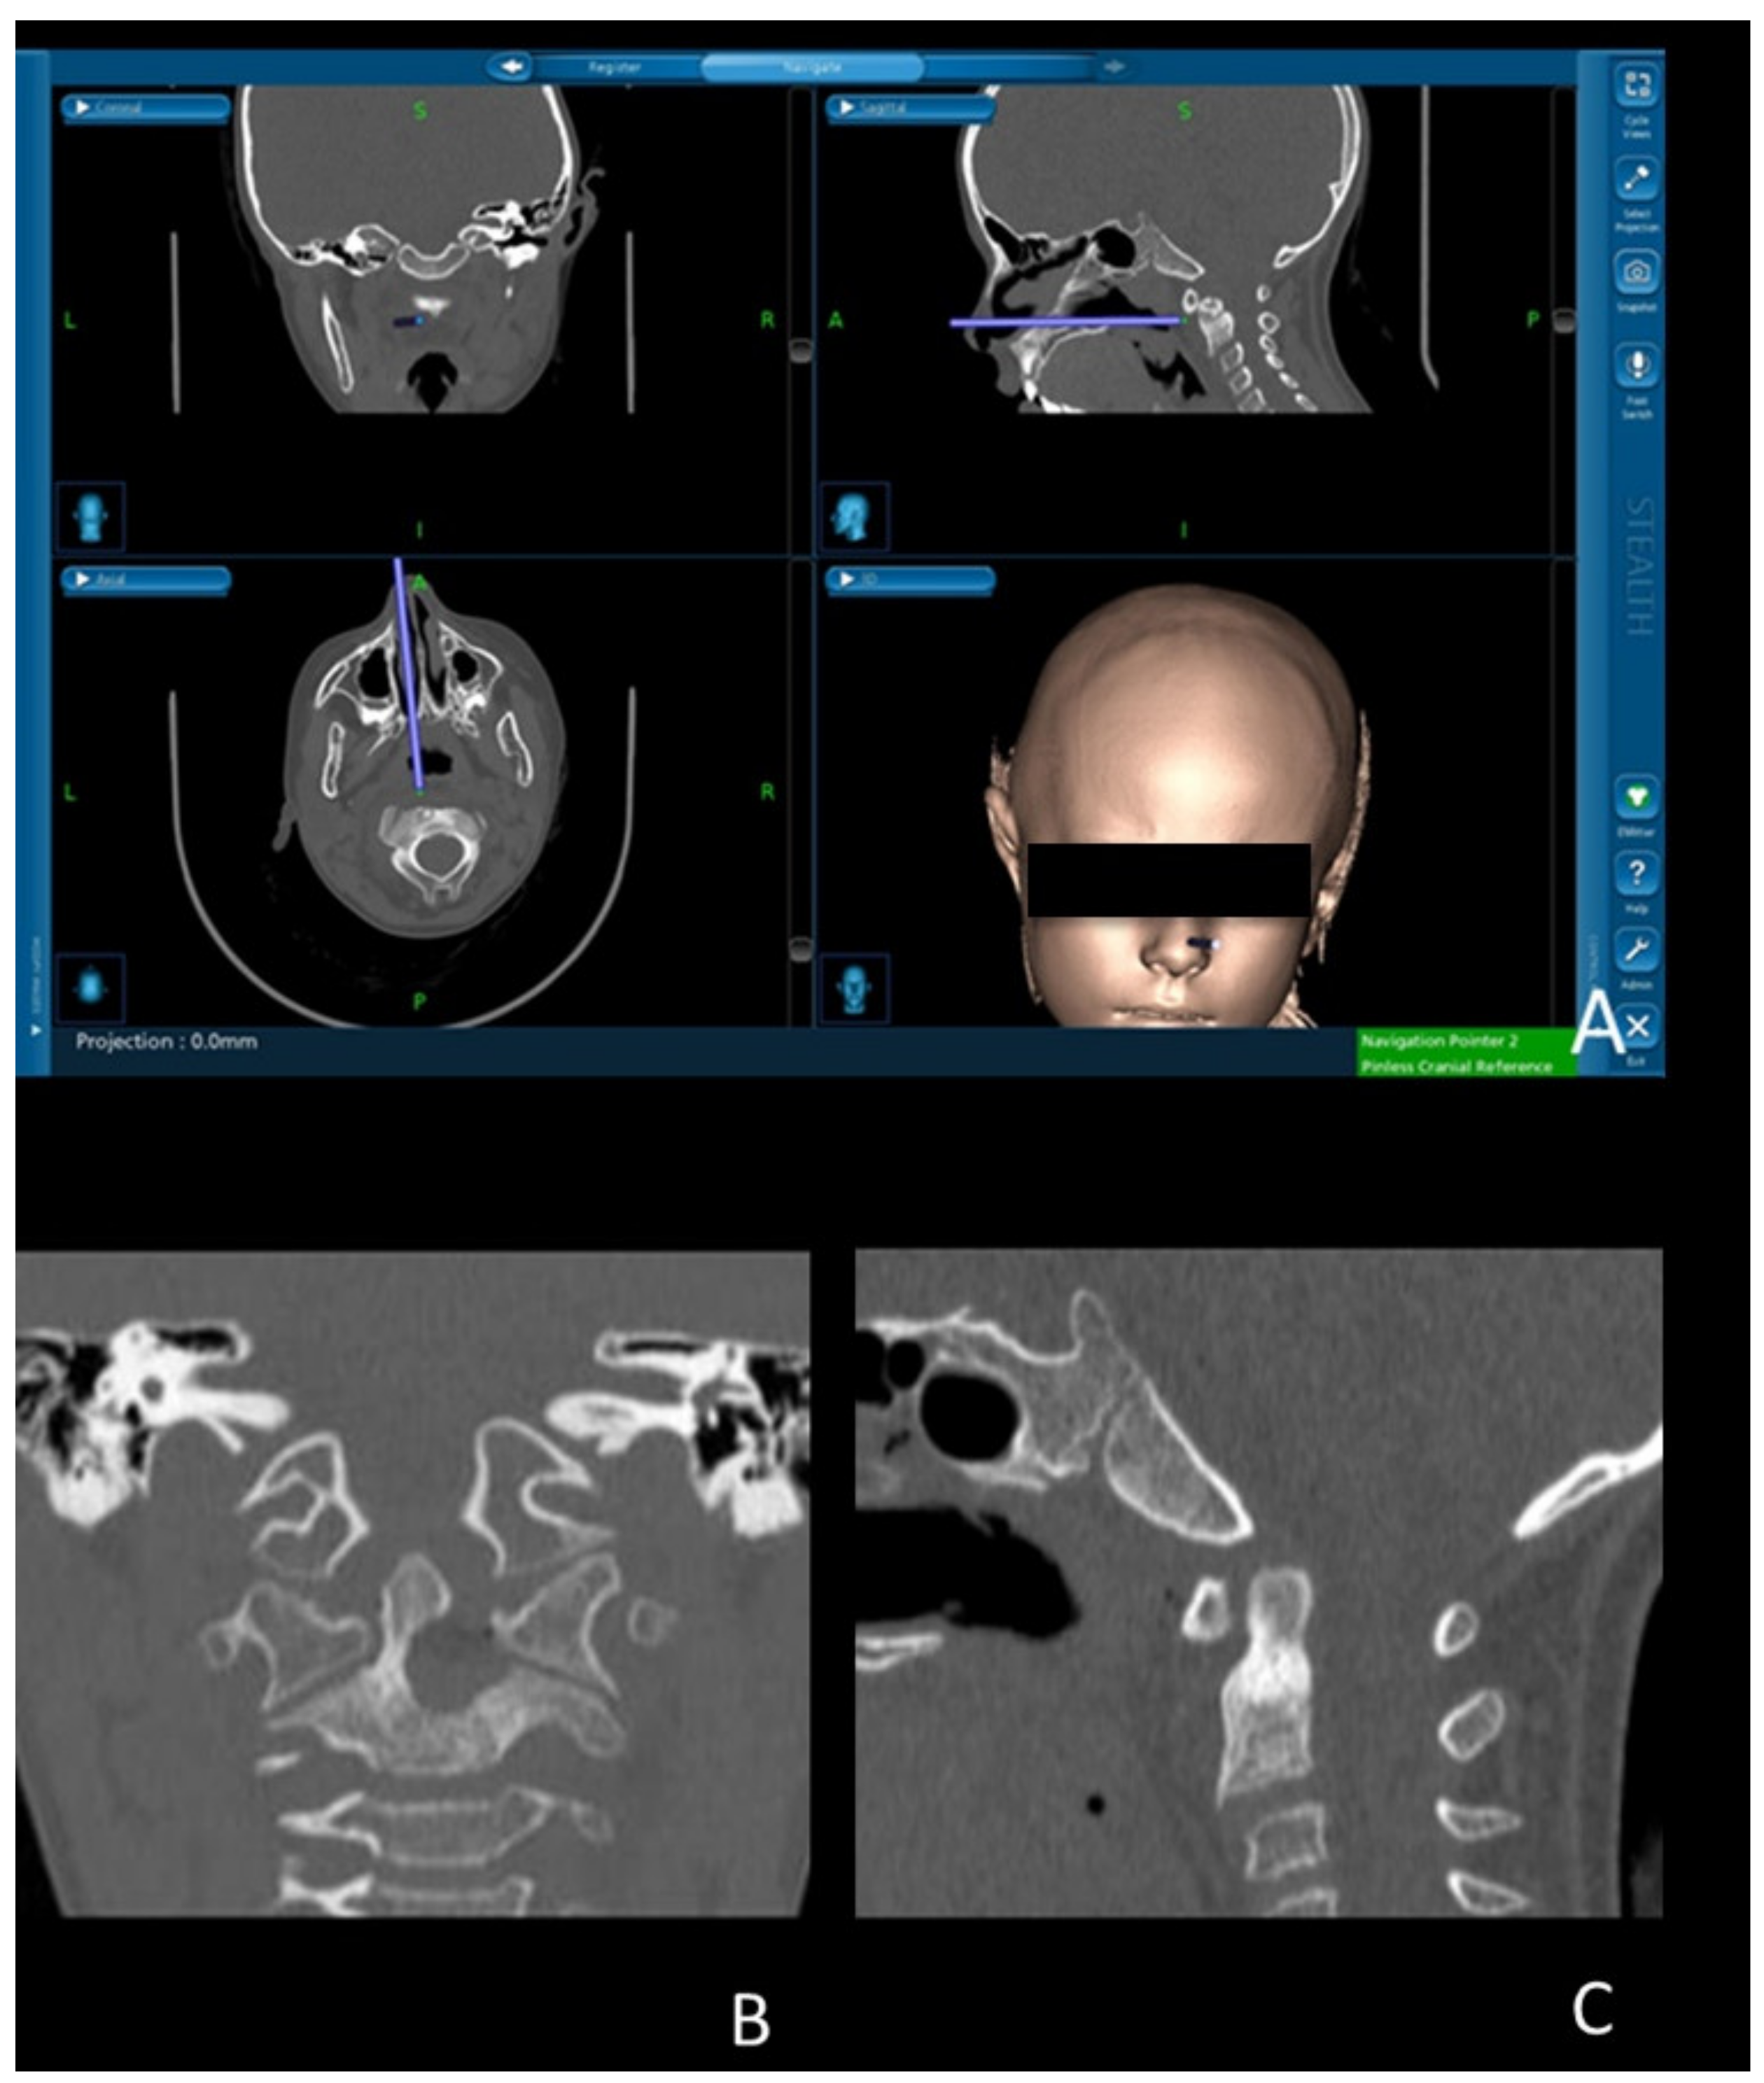

2.1. Technical Note

2.1.2. Surgical Procedure